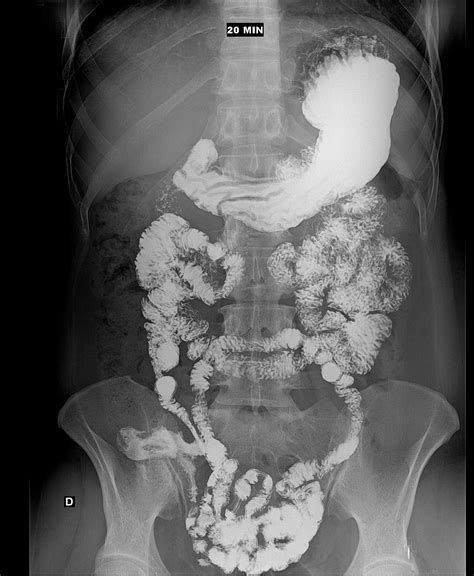

Seriada Esofago-Gastro-Duodenal y Trasito de ID

Están indicados cuando se sospecha seudoobstrucción intestinal o compromiso digestivo de afecciones tales como esclerodermia o enfermedad de Chagas.

Se usa contraste + Rx cada cierto periodo de tiempo para evaluar el transito intestinal y motilidad.